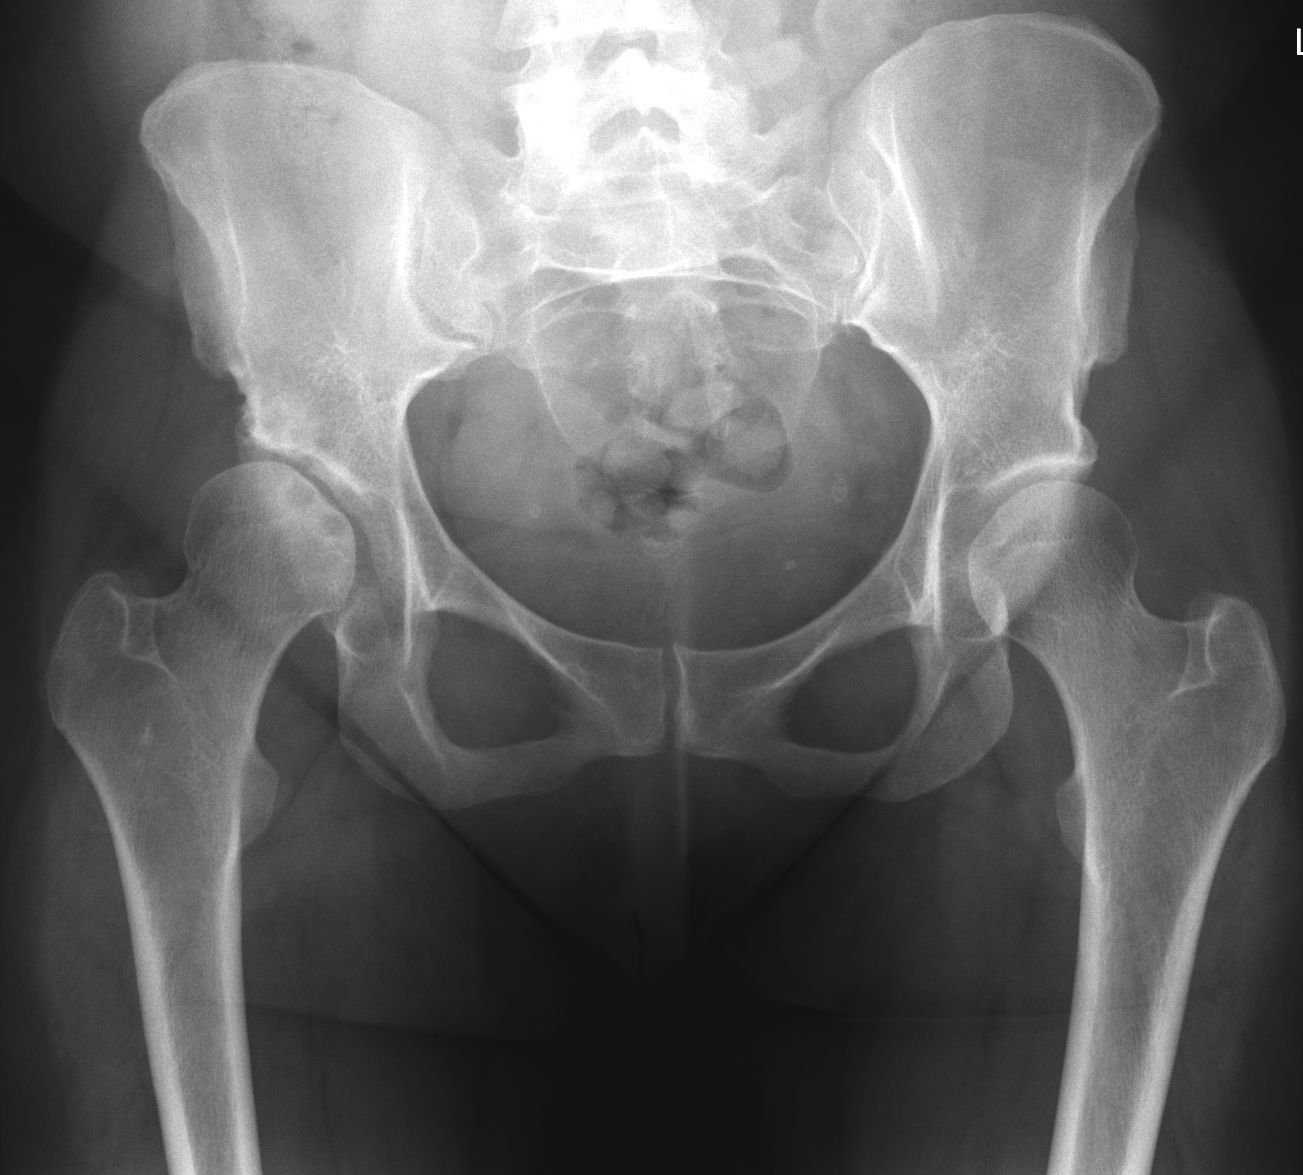

Osteonecrosis of the hip is a painful condition that occurs when the blood supply to the bone is disrupted. Because bone cells die without a blood supply, osteonecrosis can ultimately lead to destruction of the hip joint and arthritis. Osteonecrosis is also called avascular necrosis or aseptic necrosis. Although it can occur in any bone, osteonecrosis most often affects the hip. More than 20,000 people each year enter hospitals for treatment of osteonecrosis of the hip. In many cases, both hips are affected by the disease.

The hip is a ball-and-socket joint. The socket is formed by the acetabulum, which is part of the large pelvis bone. The ball is the femoral head, which is the upper end of the femur (thighbone). A slippery tissue called articular cartilage covers the surface of the ball and the socket. It creates a smooth, low friction surface that helps the bones glide easily across each other.